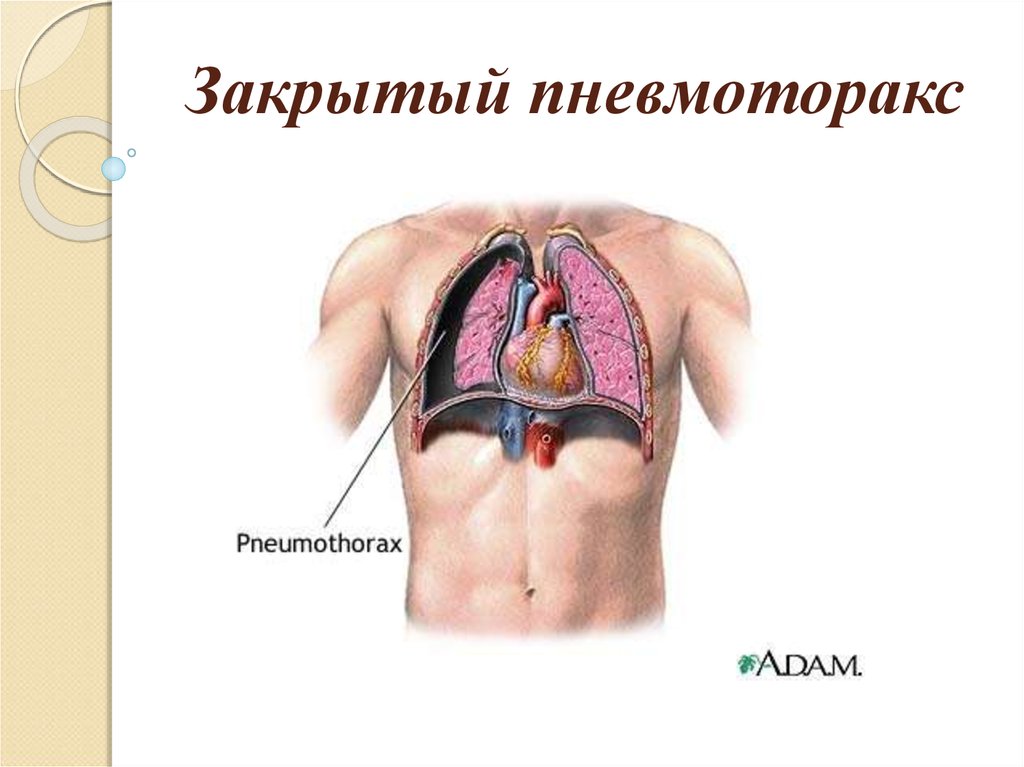

Схемы дыхания: Пневмоторакс на изображениях